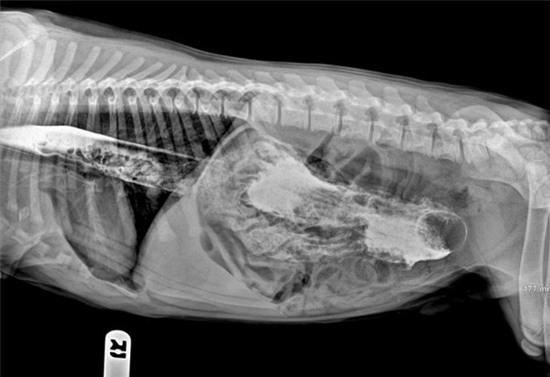

Khóc thét trước những dị vật nguy hiểm nằm gọn trong dạ dày thú cưng 4

Chú vẹt cảnh nằm gọn trong dạ dày chú trăn cưng của một gia đình sống tại bang Kentucky, Mỹ.